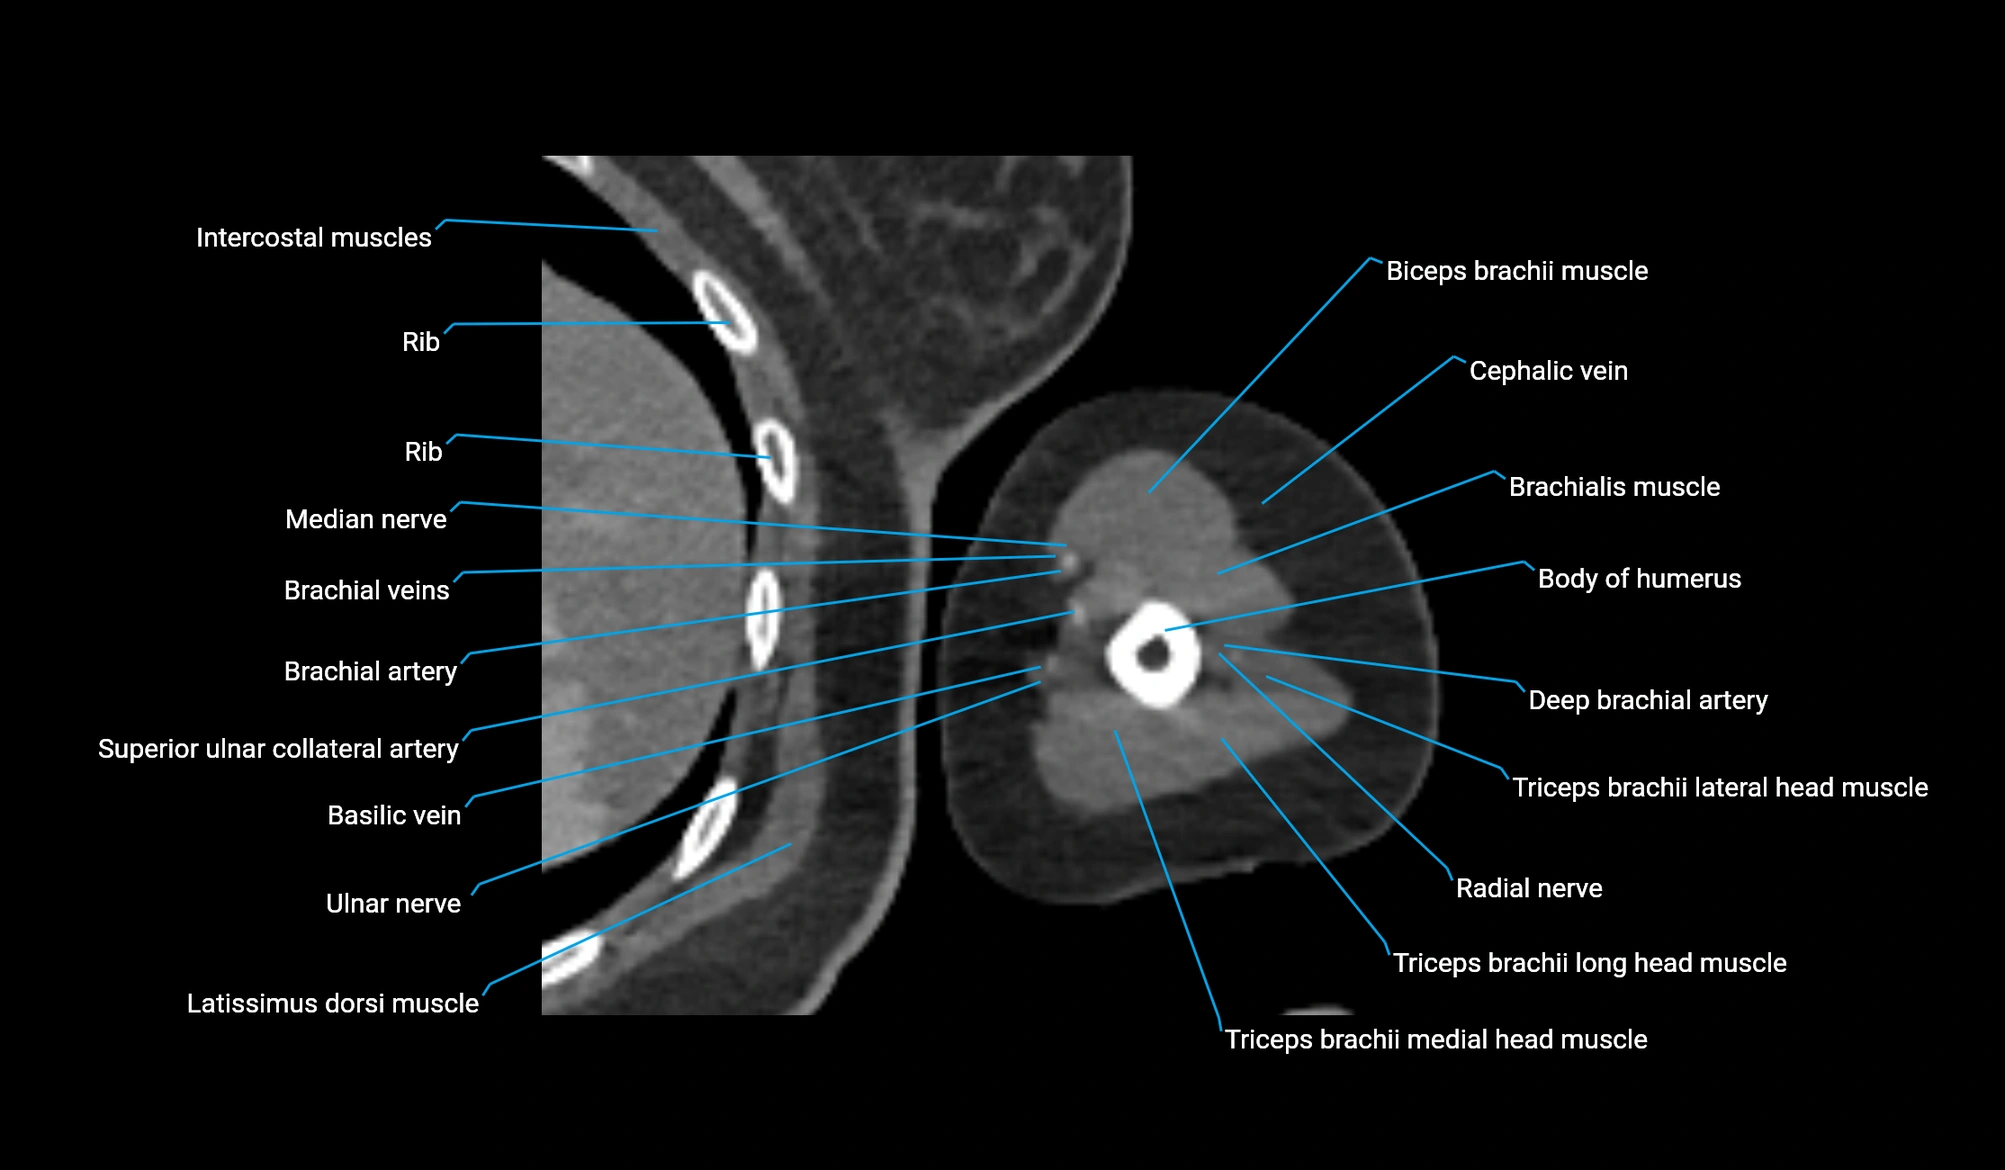

- Body of humerus

- Brachial artery

- Brachialis muscle

- Cephalic vein

- Deep brachial artery

- Long head of triceps brachii muscle

- Lateral head of triceps brachii muscle

- Medial head of triceps brachii muscle

- Median nerve

- Radial nerve

- Superior ulnar collateral artery

- Basilic vein

- Biceps brachii muscle